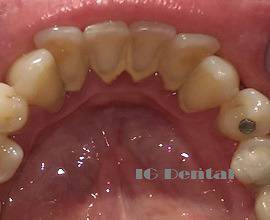

Зъбният камък представлява налеп от органична материя, храна, калциеви карбонати и фосфати, мъртви клетки от устната лигавица и др. Образуването на зъбен камък е сложен процес, свързан от една страна с тези вещества, а от друга с вида и секрецията на слюнчените жлези. Най-бързо зъбен камък се натрупва по задните повърхности на долните фронтални зъби и предните на горните кътни зъби. Там са и местата, къдети се излива слюнката от слюнчените жлези.

Скоростта на натрупване на зъбен камък е индивидуален процес, свързан с особеностите на слюнчената секреция, храната която приемаме, орално – хигиенните процедури които извършваме и други индивидуални фактори водещи до ускорявване или забавяне на процеса. Стуктурата на зъбния камък е пореста, което я прави идеална за развитие на микроорганизми, които след населването си започват да действат деструктивно върху зъбите и венците.

Най-честите проблеми, до които води натрупването на зъбен камък са пародонтит/пародонтоза, зъбен кариес и лош дъх. Навлезни веднъж в пориозната структура на зъбния камък, микроорганизмите не могат да бъдат премахнати с ежедневните хигиенни процедури. Това води до постоянното увреждане на структурите върху които се намират. Затова е препоръчително редовното професионално почистване. То се извършва на 6 месеца за пародонтално здрави пациенти и 3 или 4 пъти годишно за такива с пародонтит/пародонтоза. Премахването на зъбния камък се извършва със специални ултразвукови инструменти, като това го прави бързо приятно и безболезнено. След щателно почистване е необходимо зъбите да бъдат полирани, като това води до леко избелване на цвета им и до заличаване на малките неравности, оставени от зъбния камък. Полирането на зъбните повърхности е необходимо, защото в противен случай натрупването на нови отлагания става много по – бързо.